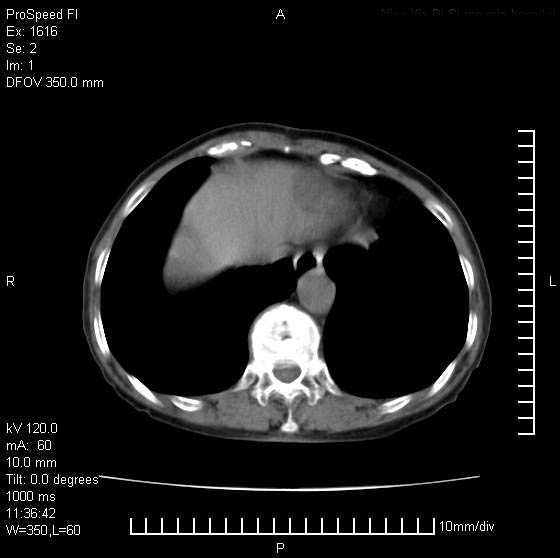

患者无明显临床症状,肝左叶发现一个圆形密度不均的低密度灶,边界较清楚,大小37x45mm,ct值35-70,患者犹豫做增强,如有增强片,我再发上,现先请各位老师会诊.

左肝外叶可见较大圆形低密度影,病灶可见较光整清晰边界,病灶内可见多量条状稍高密度影,右肝前叶亦可见圆形结节状低密度影,边界清晰,密度均匀,考虑1肝多发囊肿,左肝囊肿内出血2肝包虫病3左巨块型肝癌出血合并右肝转移或合并右肝囊肿

病灶内高密度影,从ct值上看是血的密度还是某种纤维组织呢?似乎有内缘有包膜,肝脏各叶比例略失调,脾脏有点大.

hcc(巨块型)伴出血,突破肝包膜,肝胃韧带内,腹主动脉旁淋巴结转移;肝硬化

肝左叶不均匀占位,内有斑片状高密度出血灶,内侧缘似有假包膜,腹主动脉周围及肝门区结构紊乱,似有增大淋巴结,考虑:肝左叶hcc并淋巴结转移。建议增强扫描除外其他。